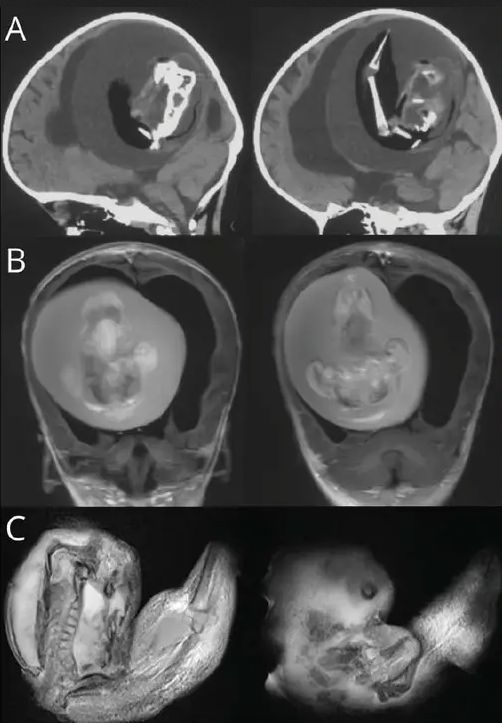

Po tym, jak matka zgłosiła się z córką do szpitala, lekarze wykonali tomografię komputerową czaszki. Badanie ujawniło "tkanki miękkie, kości przypominające kończyny i mieszane cienie tkanki kostnej w obszarze wewnątrzczaszkowym".

Zdecydowano, że dziewczynka zostanie poddana kraniotomii. W mózgu dziewczynki odkryto płód siostry bliźniaczki dziecka. Miał 18 cm długości, usta, oczy, głowę, włosy, ułów, przedramię, dłonie i stopy oraz kości długie i kręgosłup.

Lekarz usunęli zarodek, jednak krótko po operacji roczna dziewczynka straciła przytomność i pojawiły się drgawki. Uszkodzenie mózgu było zbyt poważne, a mała pacjentka zmarła 12 dni po zabiegu. Opis tego przypadku opublikowano właśnie w czasopiśmie naukowym "American Journal of Case Reports".